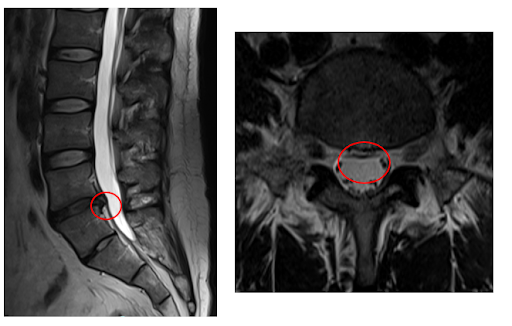

┃治療後の経過

術後は少しずつ痺れが軽減しており、ヘルニアの縮小も認められました。